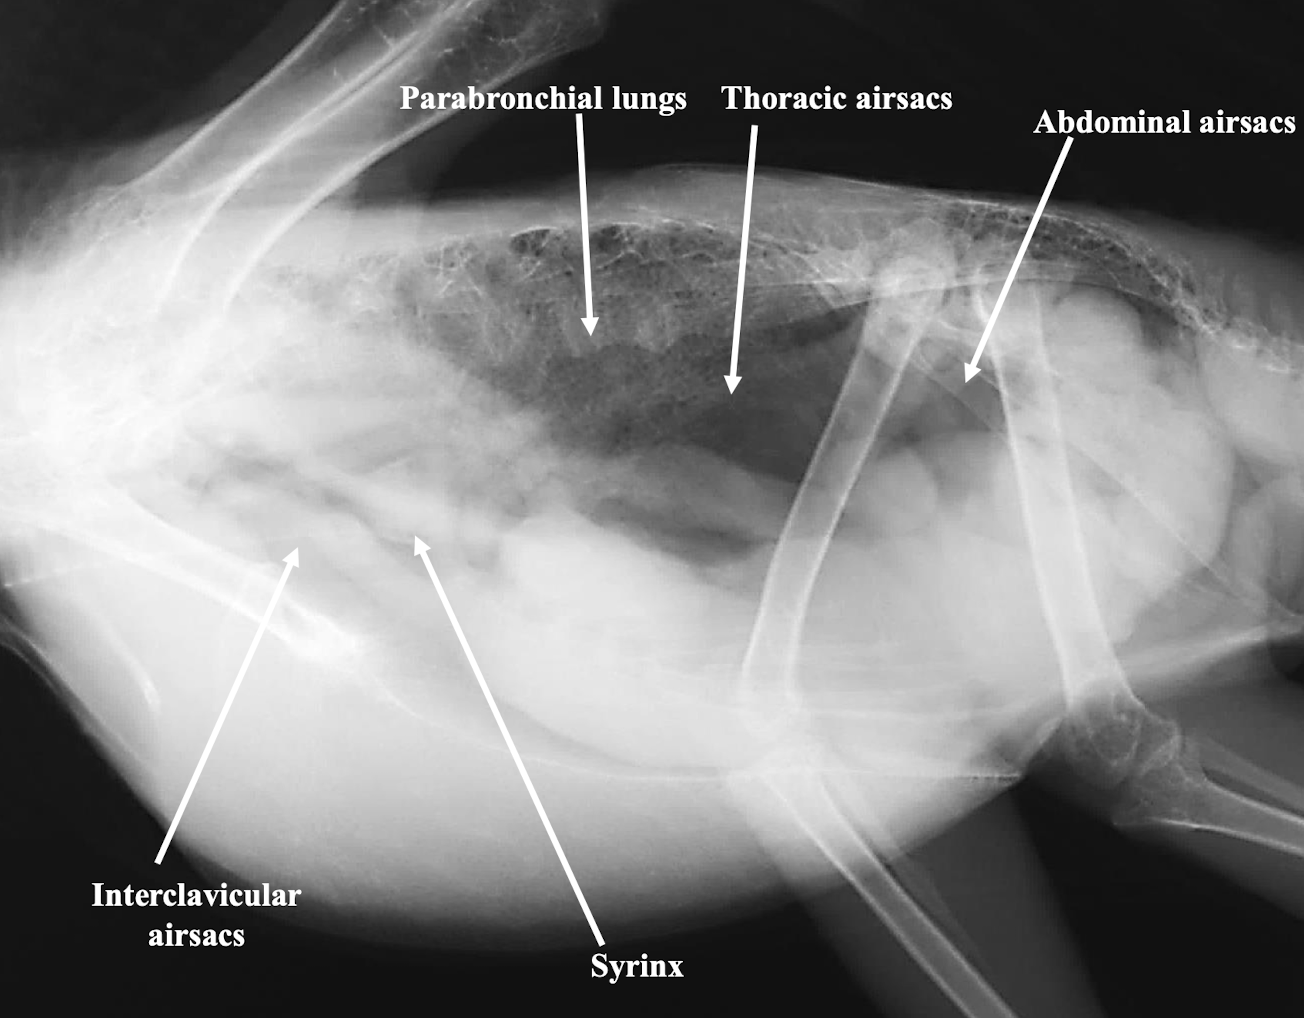

Which major air sacs are typically identified in avian respiratory imaging?

Interclavicular, cranial thoracic, caudal thoracic, and abdominal airsacs.